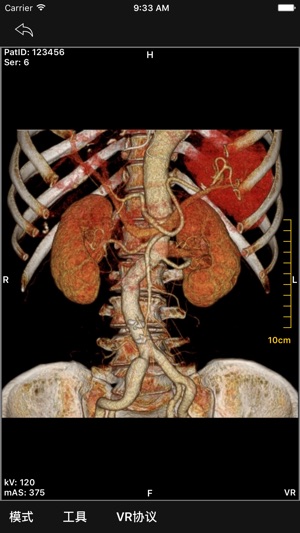

- 3D显示:包括MIP,Volume Rendering模式

- 3D图像切割